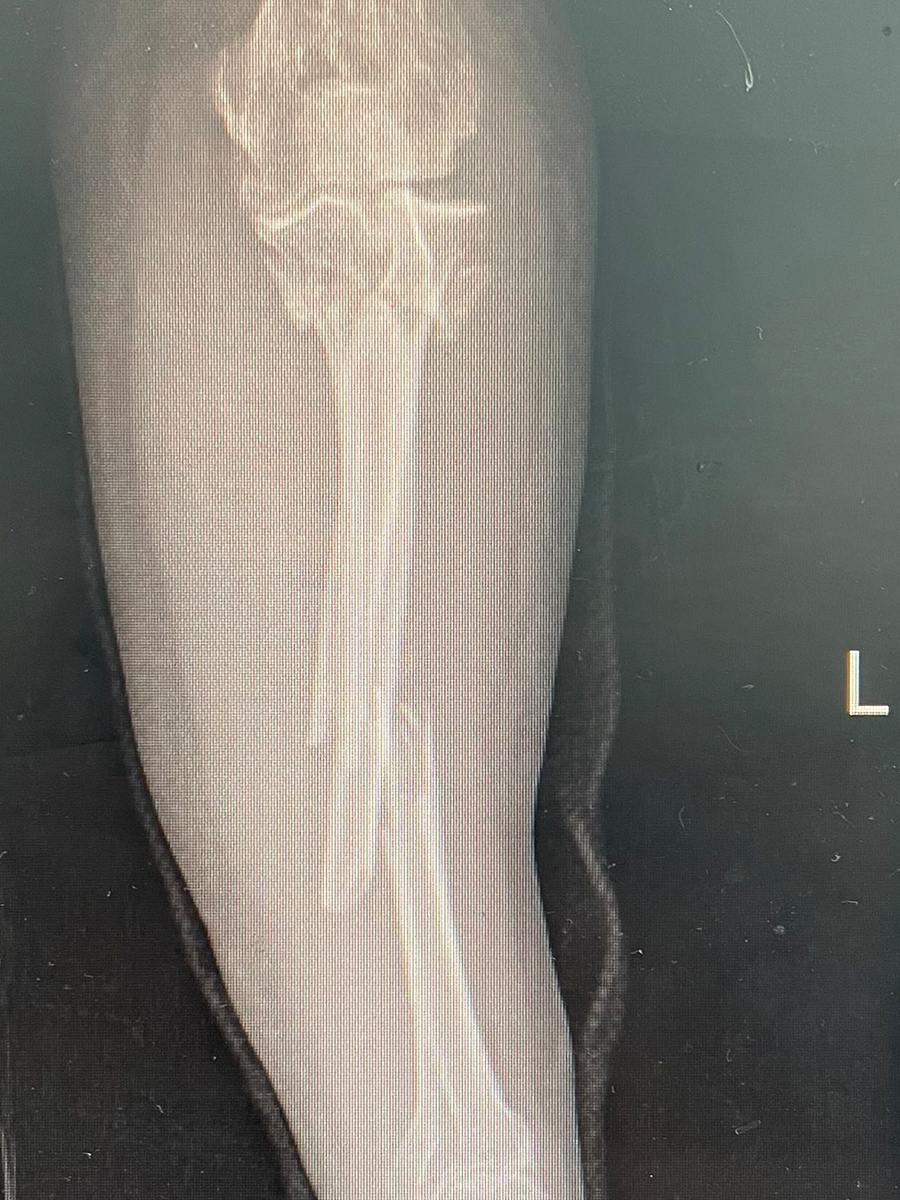

交通事故伤残鉴定需要拆除内固定吗?交通事故最常见的伤情就是骨折,而现在医院治疗骨折最常见的方法就是内固定手术,也就是用金属螺钉、钢板、髓内针、钢丝或骨板等物直接在断骨内将断骨连接固定起来,保持骨折的位置和稳定性,促进骨折愈合。很多经过内固定手术的当事人就会有一个疑问,我身体里面还有钢钉钢板...